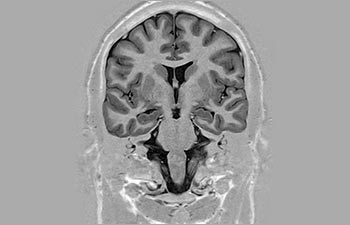

Mayor fiabilidad diagnóstica en neurooncología

Encuentre la aplicación clínica adecuada a sus necesidades